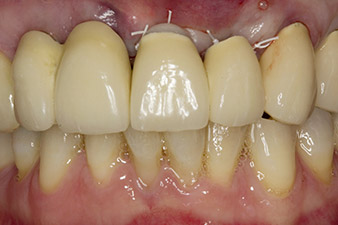

Fig. 1: The initial radiological findings revealed a splinted crown restoration requiring replacement. When the restoration was removed, teeth 21 and 22 were unintentionally extracted along with it.

When the patient first presented, teeth 21, 22 and 23 had been restored with splinted crowns, now 19 years old, which were bonded to the implants at positions 12/11 by an attachment (cf. Fig. 2).

The x-ray revealed horizontal bone loss around teeth 21 and 22 (Fig. 1). When the crown block was removed, these teeth were unintentionally extracted with it.

Tooth 23 displayed a horizontal-coronal fracture and was restored with a post and core build-up for the temporary restoration. The plan was to place a zirconium oxide bridge on the existing implants at positions 12 and 11 and to place two new implants at positions 22 and 23.